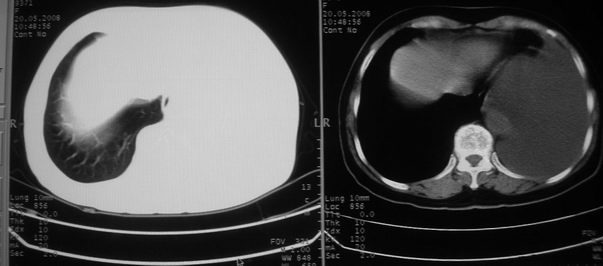

以下是引用w_jianhua在2008-5-22 12:59:00的发言:[br]1.左肺上叶肺癌并左侧胸腔积液可能性大。2不除外支气管内膜结核并包裹性胸腔积液,建议支气管镜检3.左肺下叶肺大泡,肺气肿